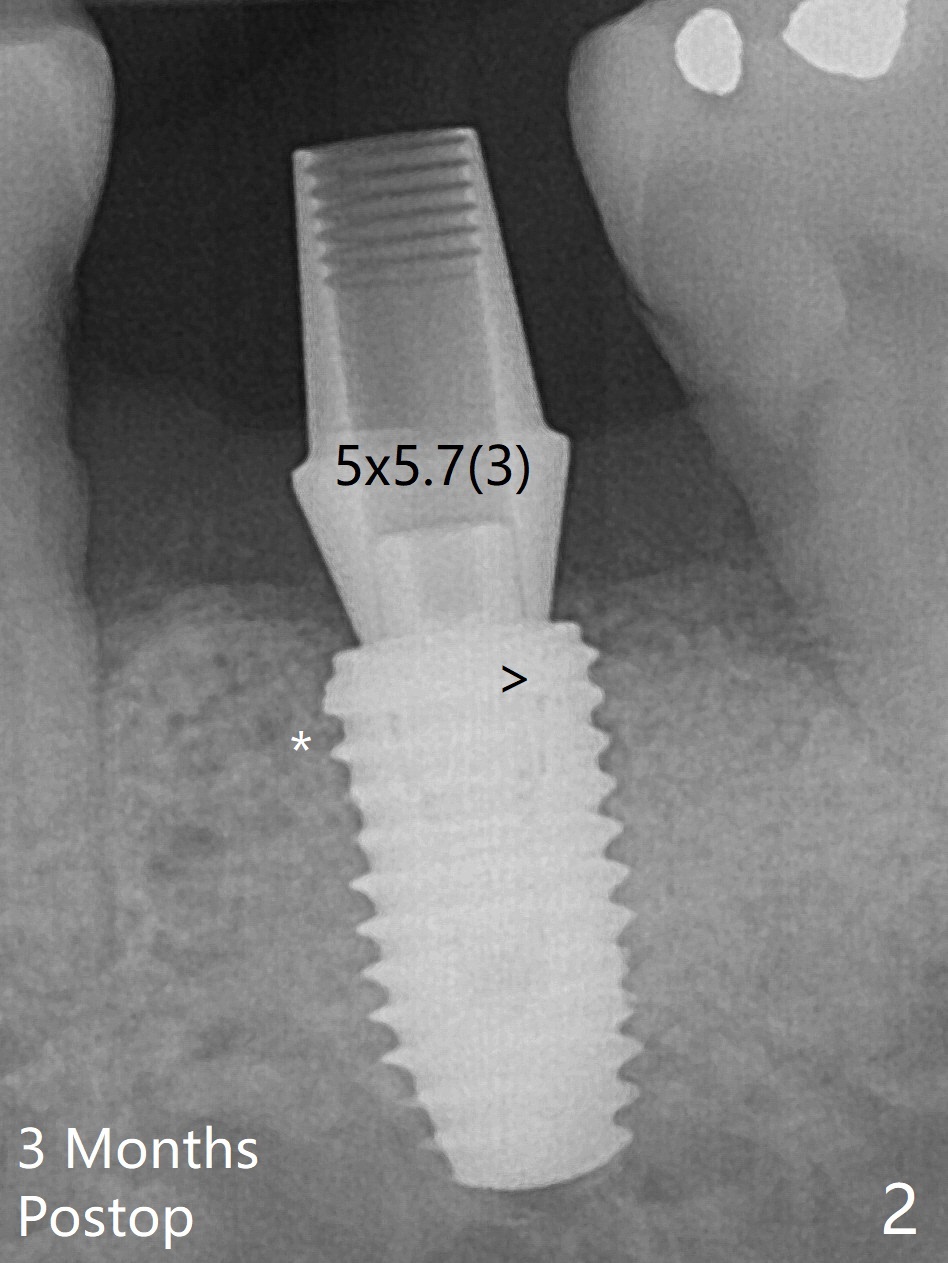

60岁男,吸烟,左下7位点保存后5个月,使用导板环形刀等常规植入5x10毫米IS植体,使用profile drill后,放置6x5毫米愈合基台(图一)。术后3个月,原来近中牙槽窝完全愈合(图二:*),放置5.5x5.7(3)毫米IBS基台,好像没有完全就位,更换4.5x7(4)毫米UF基台就位仿佛改善(图三),降低基台高度后取模。